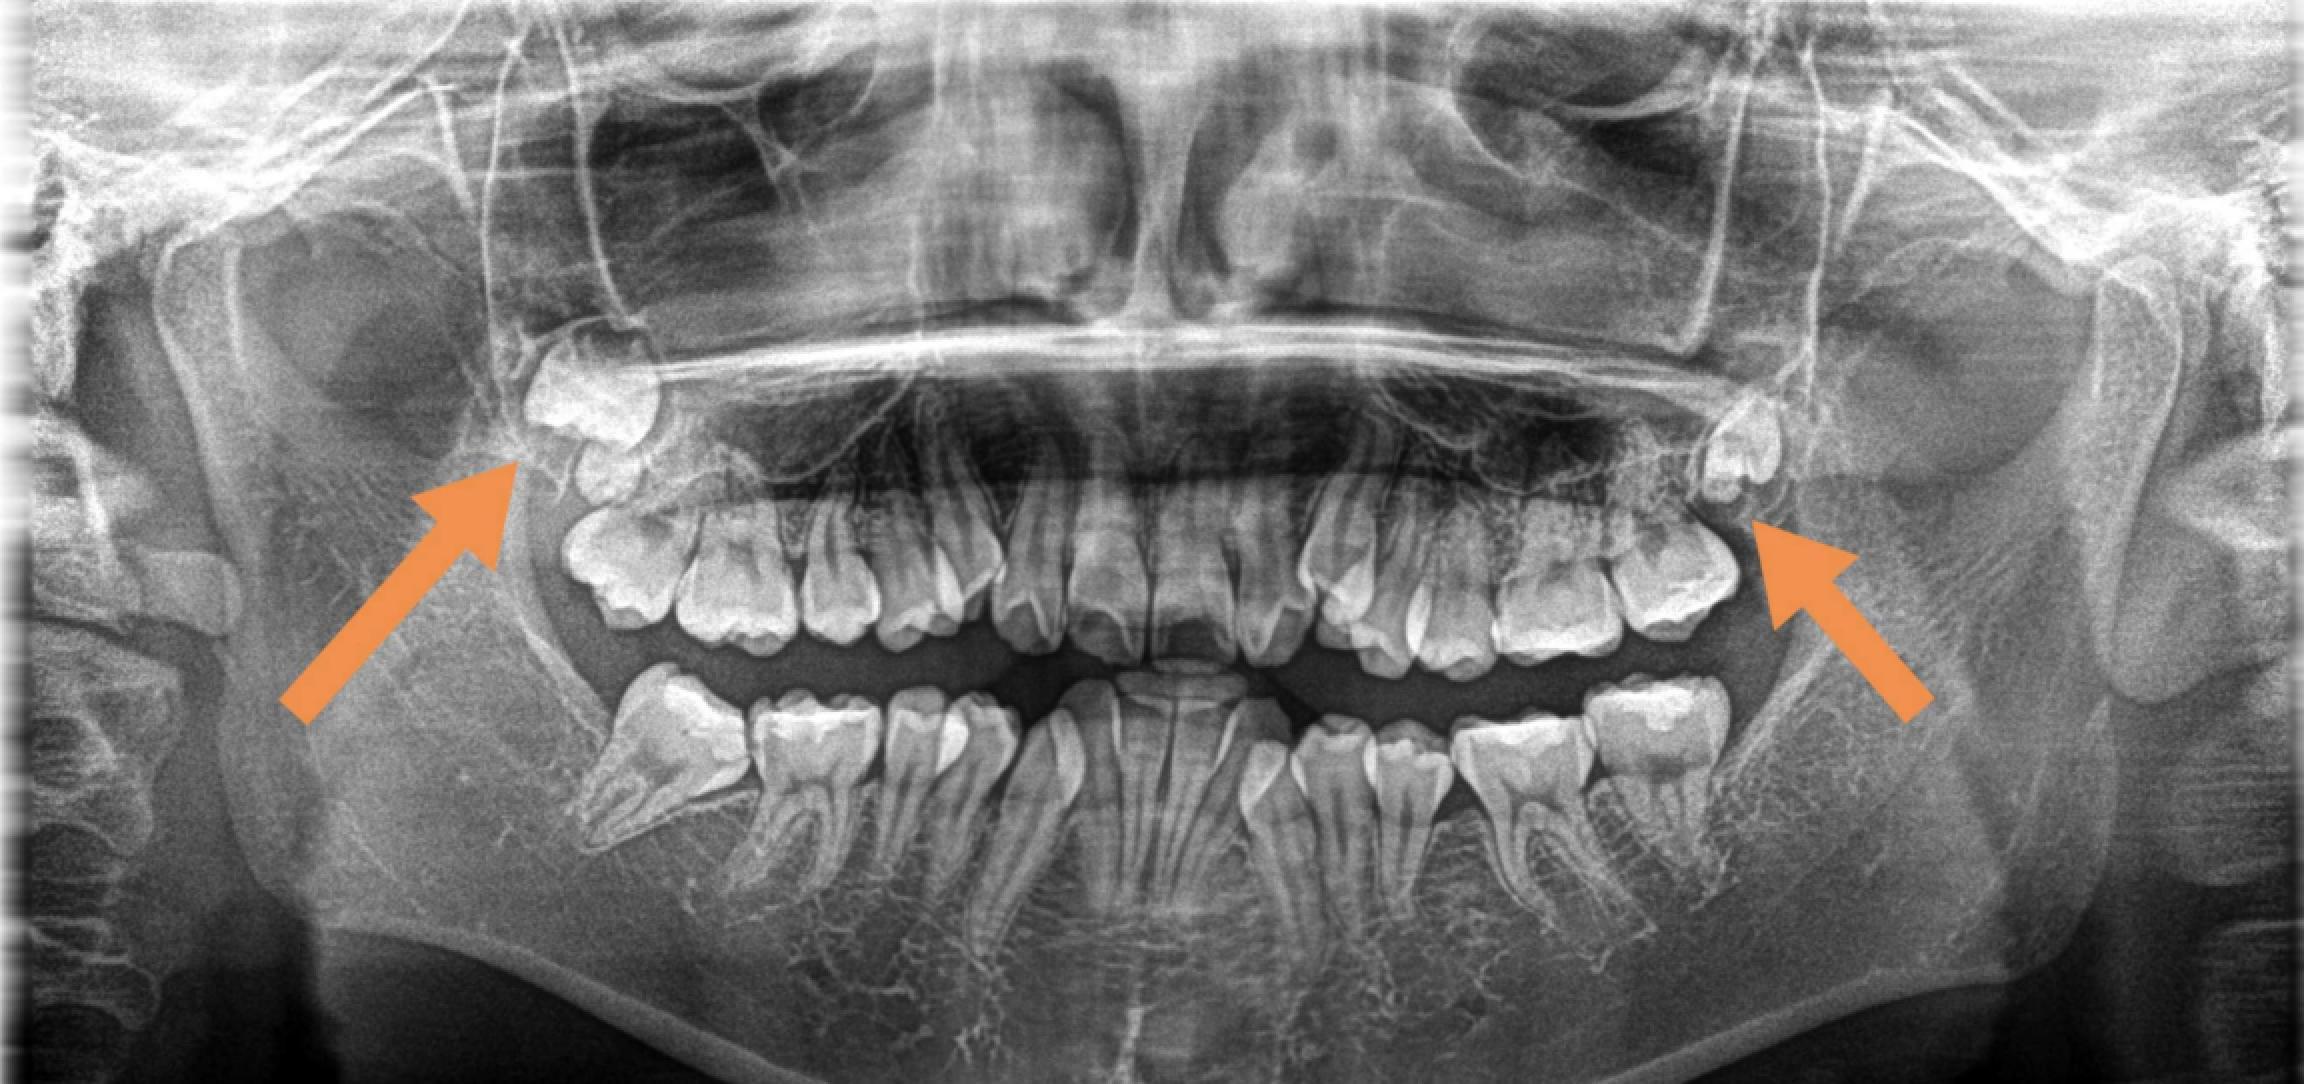

二、拔牙前為什么要先拍片子?因為就算同樣是拔智齒,每個人的牙齒情況也不盡相同。

拔牙前拍 X光片可以讓醫(yī)生看到肉眼看不到的牙根形態(tài)、生長狀態(tài)。

根據(jù) X光片的結(jié)果,醫(yī)生可以更地評估拔牙的難度,定制拔牙的方案,向患者更好地解釋一些可能存在的風險。

此外,有時候X光片還能發(fā)現(xiàn)肉眼看不見的斷在牙槽骨里的殘根,在手術(shù)時可以對拔除殘根更加地有把握。

(術(shù)前進行拍片,確定牙齒情況)